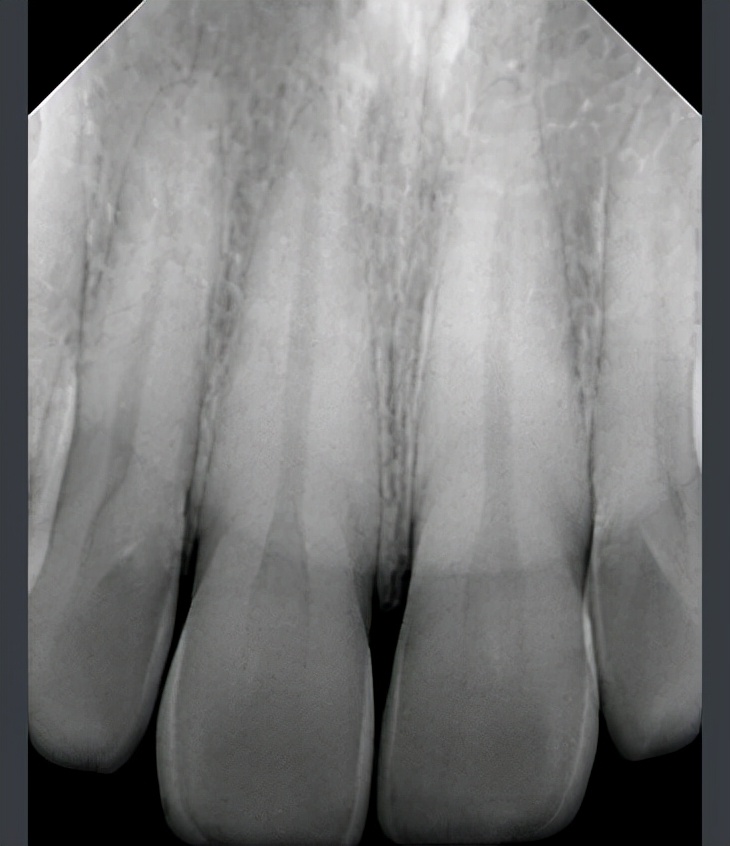

全新口内传感器,适用于牙科诊所、口腔门诊以及宠物医院。宠物用X射线拍摄。